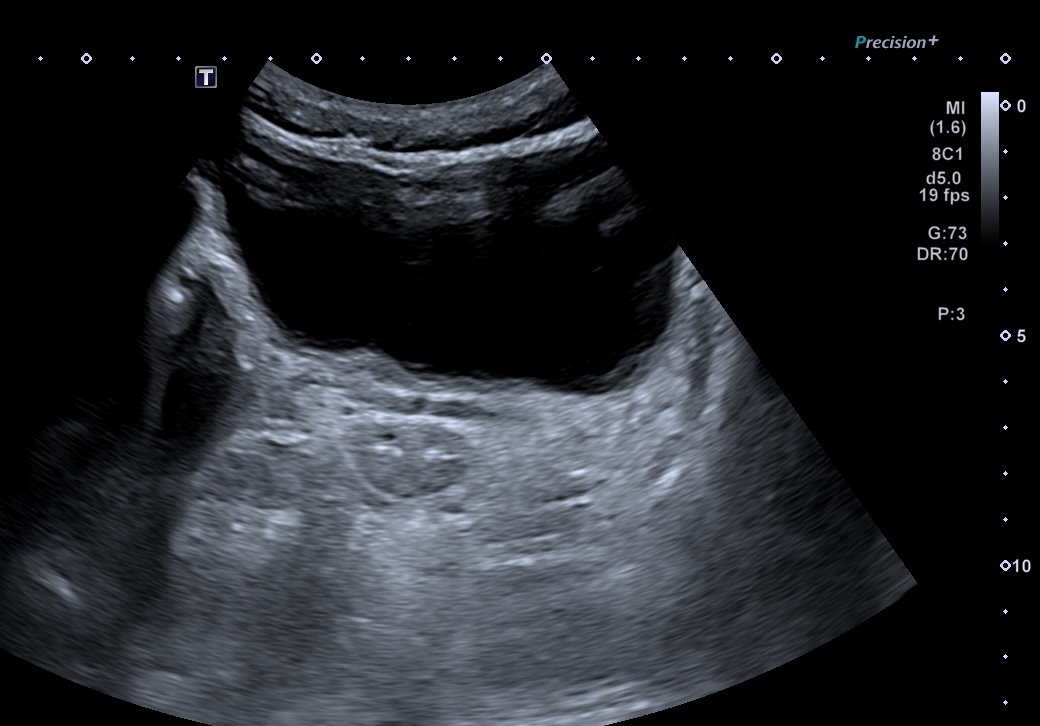

On voit successivement

La vessie

l'axe prostate-vésicule séminales

Le rectum

Même patient, coupe passant par les vésicules séminales